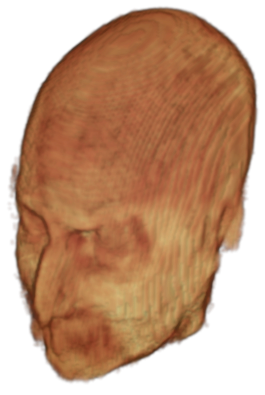

The digitalization of heath records has increased the risk of –and impact of– large scale data leaks. Although data compliance standards have been enacted to protect health records (HIPAA and GDPR), privacy of medical data is a growing concern. Three-dimensional scans such as magnetic resonance images (MRI) and computed tomography (CT), for example, contain an intrinsic privacy risk [Lotan et al.(2020)Lotan, Tschider, Sodickson, Caplan, Bruno, Zhang, and Lui]. Detailed renderings of the head can be crafted from 3D scans using techniques such as volumetric raycasting, as in Figure 1. This vulnerability can expose the patient’s identity if the renderings are matched to a face database [Mazura et al.(2012)Mazura, Juluru, Chen, Morgan, John, and Siegel, Lotan et al.(2020)Lotan, Tschider, Sodickson, Caplan, Bruno, Zhang, and Lui].

To prevent these types of attack, medical scans are currently de-identified using crude removal-based techniques [Bischoff-Grethe et al.(2007)Bischoff-Grethe, Ozyurt, Busa, Quinn, Fennema-Notestine, Clark, Morris, Bondi, Jernigan, Dale, Brown, and Fischl, Schimke et al.(2011)Schimke, Kuehler, and Hale, Milchenko and Marcus(2013)] which seek to remove privacy-sensitive parts of the head (examples in Figure 3). However, as we demonstrate, these existing techniques fail to reliably hide the patient’s identity – or they are so aggressive that they impair further medical analyses. A better solution is needed.

![]() |

Therefore, in this work, we define a new class of de-identification techniques that remodels the privacy-sensitive regions without altering the content of medically relevant data (see Figure 1). Under such a remodeling approach, the face, eyes, oral and nasal cavities, etc. should exhibit realistic appearance and structure of appropriate size, but should otherwise be independent of the original data. To solve this task, we propose a novel model called Convex Privacy GAN, or CP-GAN, that conditions on a convex hull of the skull extracted from the scan to be de-identified. The generator learns to synthesize volumes that preserve medically-sensitive regions such as the brain, while non-invertibly remodeling privacy-sensitive characteristics from the original scan.